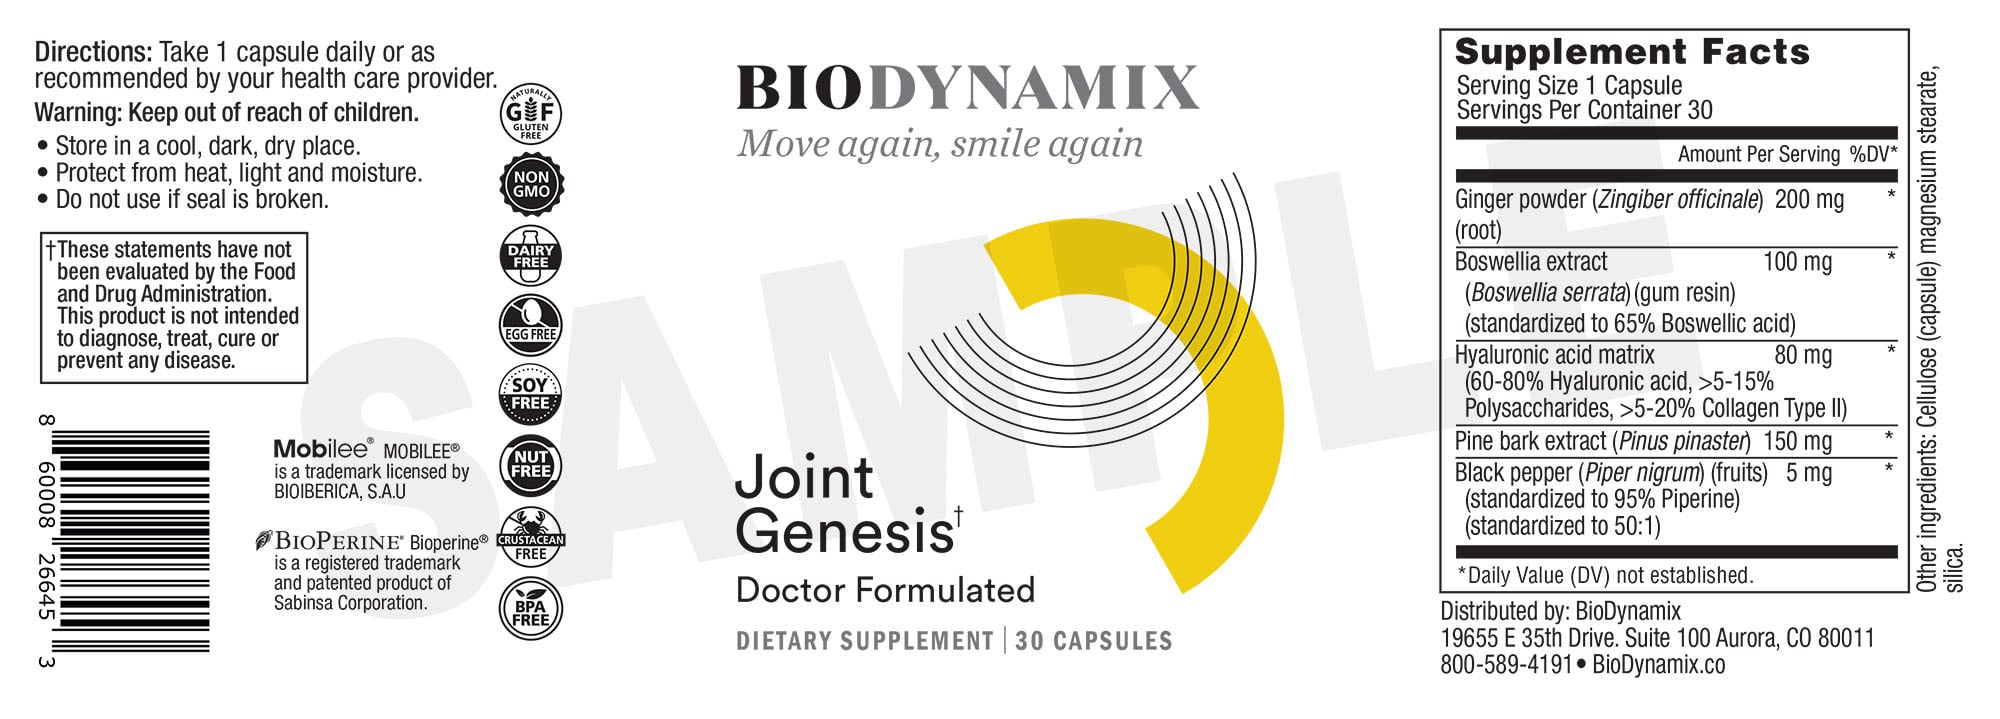

The statements and information provided on this website have not been evaluated by the Food and Drug Administration (FDA).

The products featured here are **dietary supplements** and are not intended to diagnose, treat, cure, or prevent any disease.

Statements on this website have not been evaluated by the Food and Drug Administration. Products are not intended to diagnose, treat, cure or prevent any disease. If you are pregnant, nursing, taking medication, or have a medical condition, consult your physician before using our products.